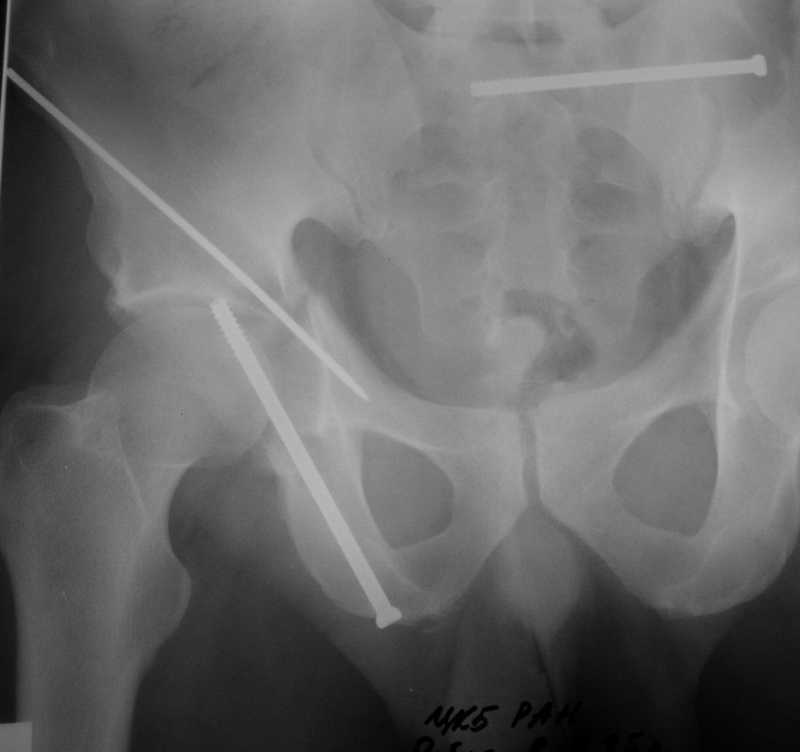

> I would like to present a case of a young (22 yo) male who suffered

> a car crush. He has combined transverse and posterior wall fracture of

> the right acetabulum as well as a nondisplaced fracture of the left

> acetabulum and bimalleolar fracture of the left ankle. Initially we did

> a combined lateral and axial traction to the right leg . The

> patient is stable now ( 6 day after the accident ), so I would like to ask for

> your opinion for the best course of treatment of the right acetabulum.

Yordan! In this case position of bone fragments is quite good. We

prefer to use miniinvasive technique. We fix posterior column by can.

screw and put 3mm pin with distal thread to the anterior column. Next day after

the surgery he may start walking with crutches.   3 month after the

surgery  we remove the pin.  In cases of maleolar fractures  we use

angle stable plates to lat. mal. and pins or screws and if

syndesmosis is intact - full loading is not forbidden.

Sending exampl pict.

Имя     : 1.jpg

Url     : http://weborto.net:8080/pipermail/ortho/attachments/20081205/95456be3/attachment-0003.jpg